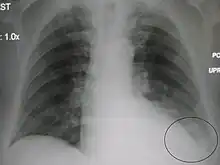

AP CXR showing right lower lobe pneumonia AP CXR showing pneumonia of the lingula of the left lung

AP CXR showing pneumonia of the lingula of the left lung Right upper lobe pneumonia as marked by the circle.